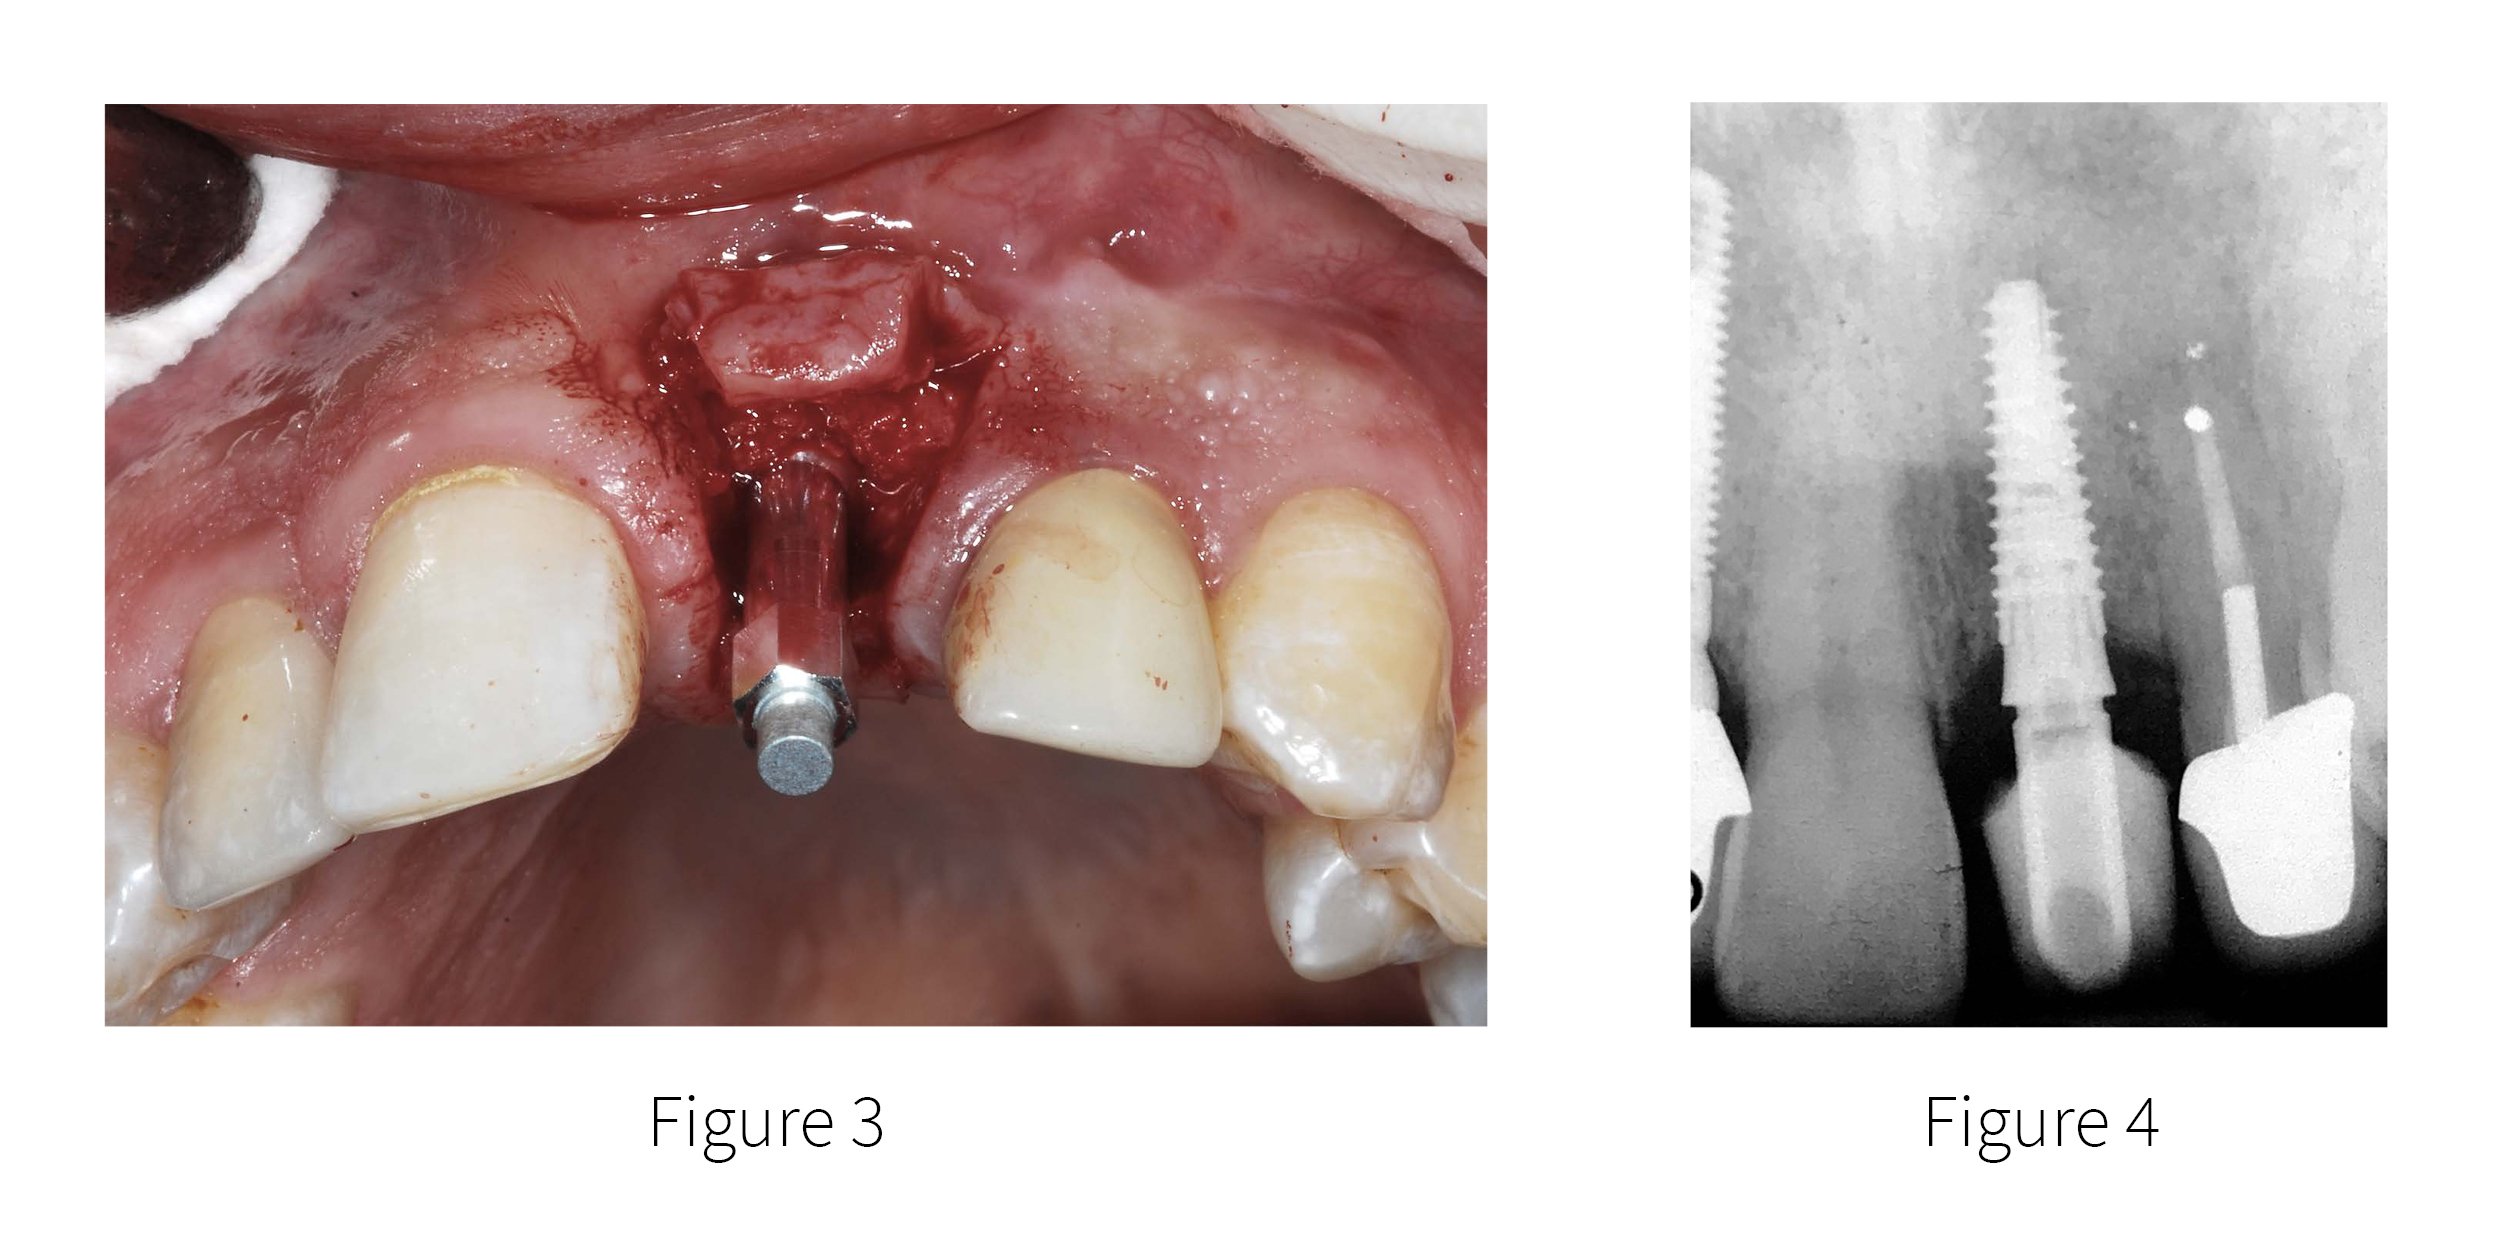

Maxillary Central Incisor Implant Supported Crown Brief Case Report Dental Implant Isq Supported by more than 1400 scientific. Four levels of coverchoose your plan The rfa is a reliable indicator for. Implant stability is a prerequisite for successful dental implants and osseointegration. Introduced rfa as a quantitative method for assessing implant stability (7). To determine the status of implant stability, continuous monitoring in an. Isq, or implant stability quotient, is a scale. Dental Implant Isq.

From dentistry.co.uk